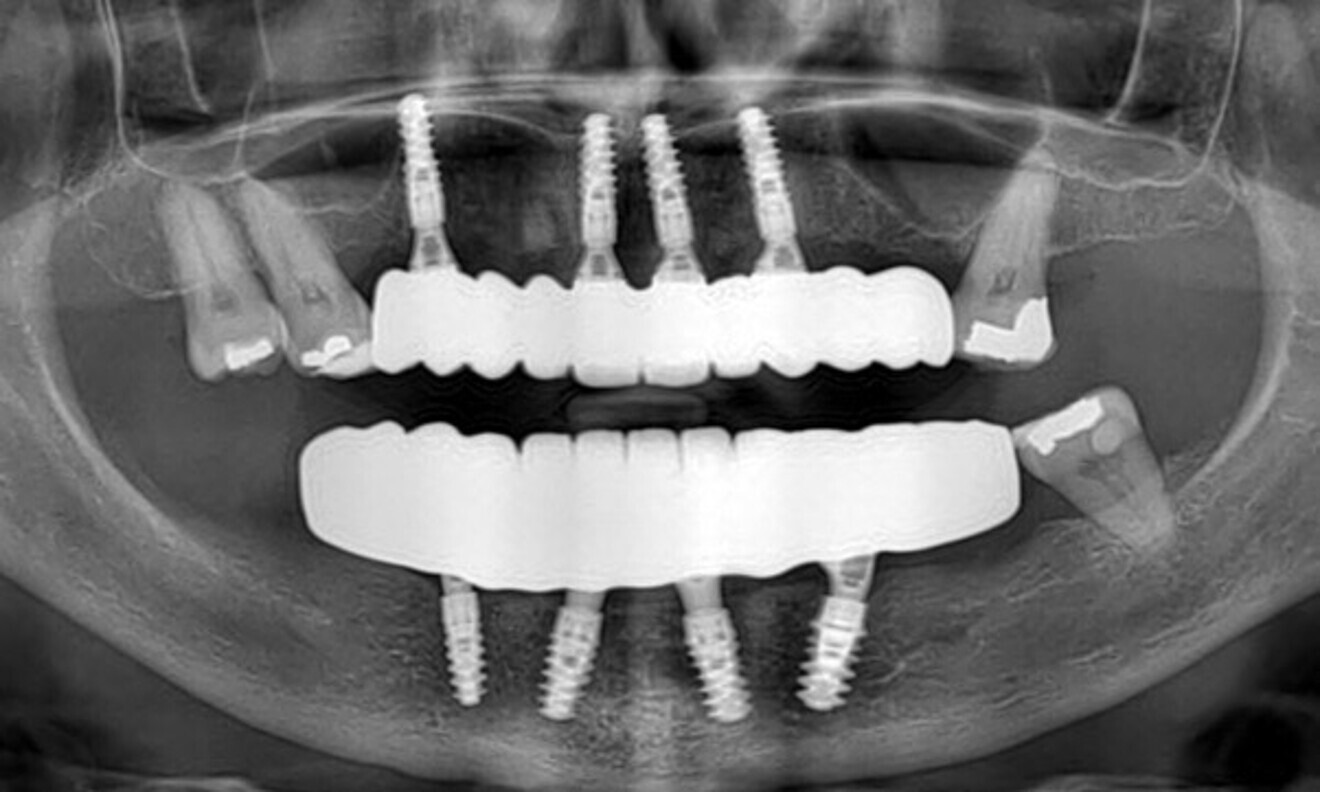

On the day that the sutures were removed, excellent healing was observed. The follow-up radiograph also confirmed the proper positioning of the implants (Figs. 67 & 68).

Fig. 67: At the suture removal appointment, excellent healing was observed, ...

Fig. 68: ... and the radiograph confirmed proper implant positioning.

A follow-up was performed six months after surgery. The radiographic examination conducted at that time confirmed the successful integration and stability of the implants (Fig. 84).

Fig. 84: The six-month post-op radiographic evaluation confirmed successful implant integration and stability.